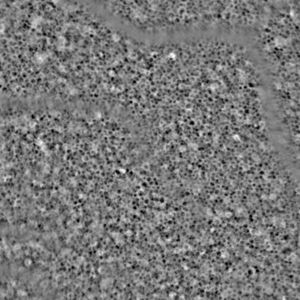

Detailliertes Bild von den Zellen im Augenhintergrund (Foto: earlysight.com) |

Mit dem neuen Gerät ist eine routinemäßige Untersuchung beim Augenarzt möglich. Es ermöglicht den Echtzeit-Einblick in die Zellen, die als erste bei einer beginnenden AMD betroffen sind. Mit den bisherigen Diagnosetechniken ist das aber nicht möglich, so Co-Autor Mathieu Künzi. "Anders als bei der bisherigen Methode, bei der Licht durch die Pupille geschickt wird, schauen wir durch die Sclera, also das Weiße im Auge." Sein Kollege Timothé Laforest ergänzt: "Dadurch haben wir einen anderen Blickwinkel auf den Augenhintergrund." Das verhindere Abbildungsfehler.

Die beiden jungen Forscher haben mit EarlySight http://earlysight.com ein Unternehmen gegründet, um ihre Entwicklung zur Serienreife zu bringen und in den Medizinmarkt einzuführen. Tests an einem Dutzend Personen ohne Augenschäden haben gezeigt, dass auf das Gerät Verlass ist. Die Bilder, die es aufnimmt, sind zehnmal genauer als jene, die mit der bisherigen Technik entstehen. Es macht die unterschiedlichen Stadien sichtbar, die die Zellen während des Alterungsprozesses durchlaufen. In den kommenden Monaten sollen 50 weitere Menschen untersucht werden, von denen einige an einer beginnende AMD leiden.